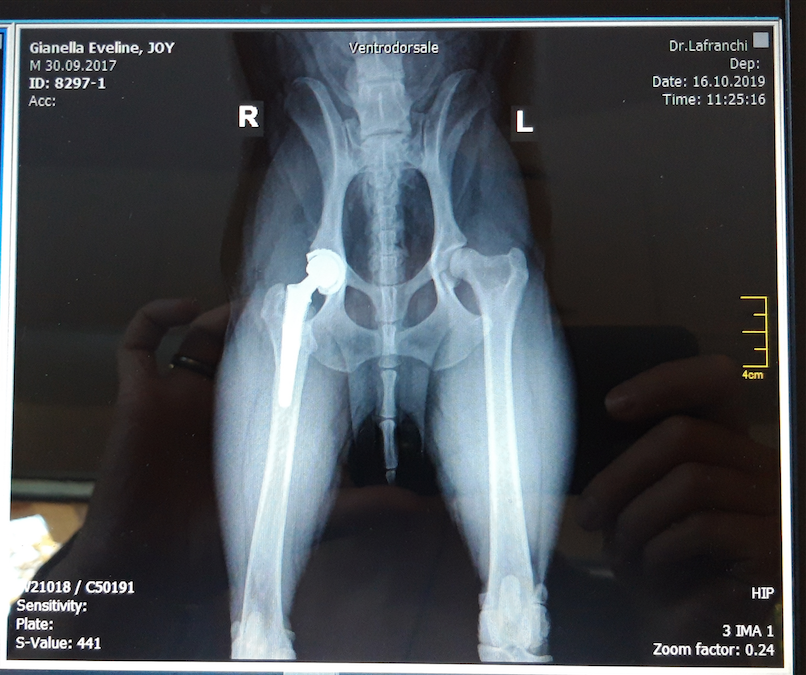

Joy sta bene e la protesi si è ben inserita.

Grazie ancora di cuore a chi l’ha reso possibile!